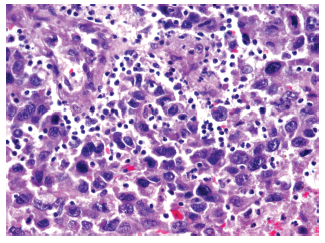

The study group included 14 patients with HCC and liver cirrhosis (45.2%) (Figure 1) and 17 patients with HCC without liver cirrhosis (54.8%) (Figure 2). The control group (patients with chronic liver disease) included 12 patients with liver fibrosis (44.5%), 7 patients with primary biliary cirrhosis (25.9%), 3 patients with autoimmune hepatitis (11.1%), and 5 patients with cirrhosis due to other causes (18.5%).

Morphologic data were characterized for signs of HCC. Trabecular-type HCC was predominant, shown in 26 patients (83.9%),versus solid tumor type, shown in 5 patients (16.1%). Degree of malignancy according to the Edmondson-Steiner system showed 8 patients (25.8%) having grade I, 10 patients (32.3%) having grade II, 9 patients (29.0%) having grade III, and 4 patients (12.9%) having grade IV (Figures 3-6 show resection of archived materials).

Figure 5. Hepatocellular Carcinoma Showing Sites of Extensive Hemorrhage and Foci of Tumor Necrosis (hematoxylin and eosin staining; ×200)

Figure 6. Hepatocellular Carcinoma With Presence of Large Hyperchromic, Atypical Nuclei With Pronounced Amount Mitosis (hematoxylin and eosin staining; ×200)